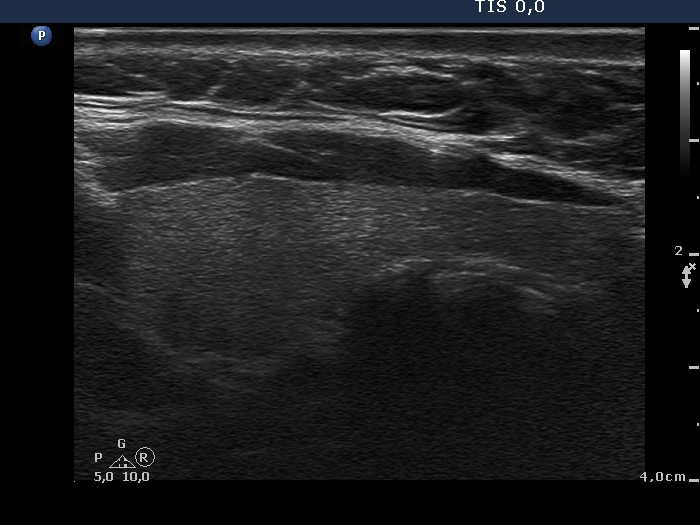

Oxyphilic adenoma - Case 21. (ultrasonographic picture 6)

Left lobe, longitudinal scan.